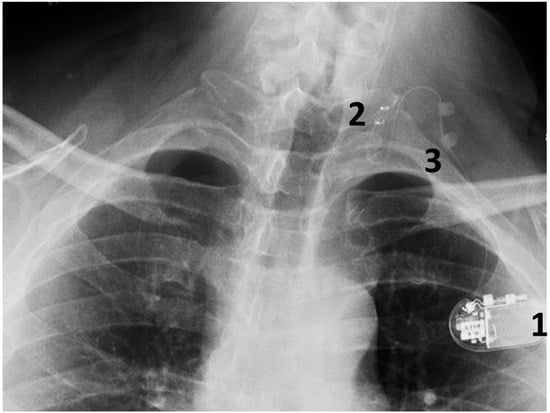

2.4. The VNS Equipment